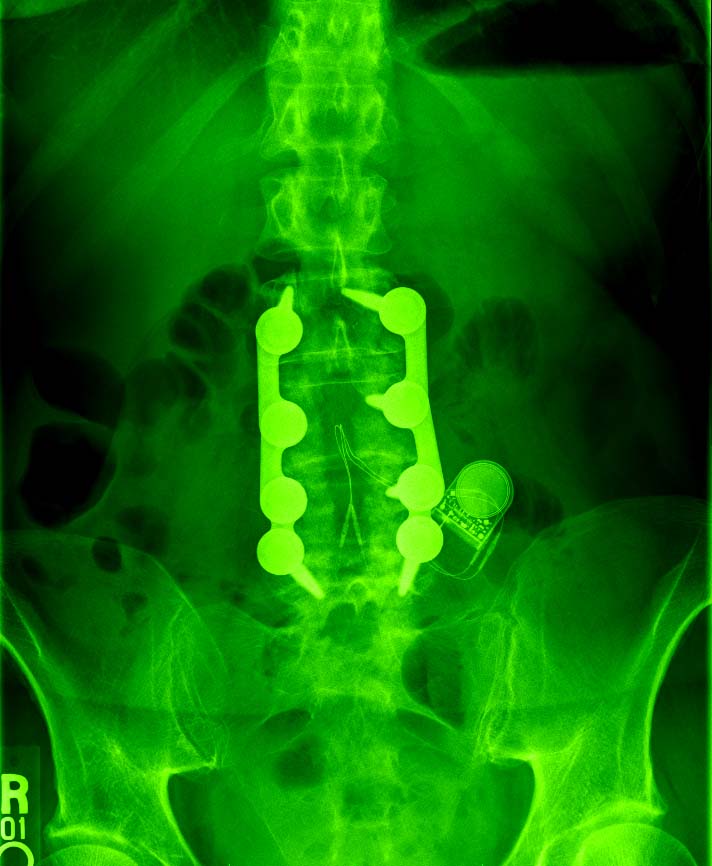

The Wonders of Modern Medicine and Computer Graphics

and the side view...